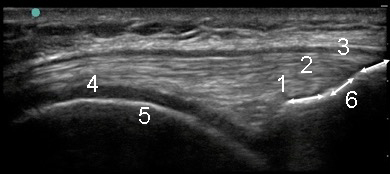

Knee Quadriceps Tendon Complex Image

- Vastus Intermedius Contribution to the Quadriceps Tendon

- Vastus Lateralis/Medialis Contribution to the Quadriceps Tendon

- Rectus Femoris Contribution to the Quadriceps Tendon

- Trochlear Hyaline Cartilage

- Distal Femur

- Proximal Patella